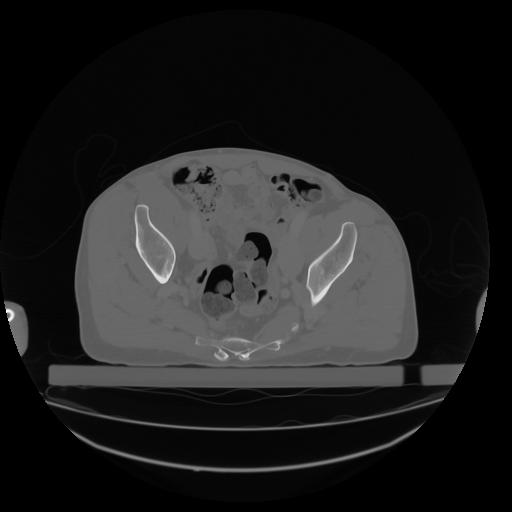

27 CUERPO,CE,Axial,3.0,CUERPO,,